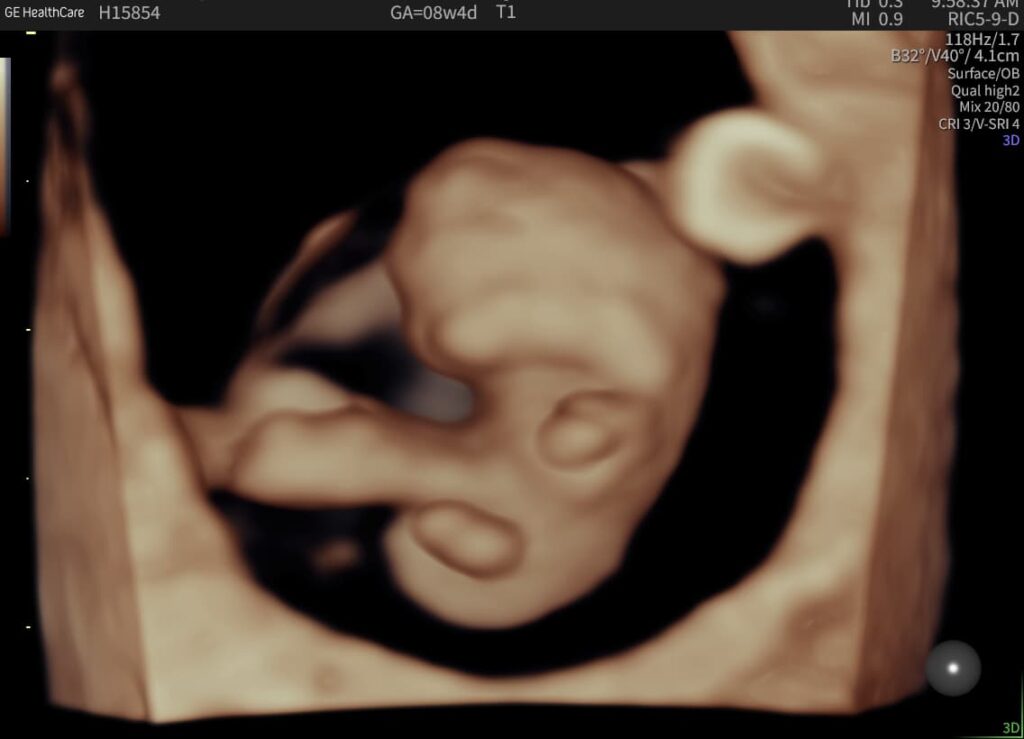

Early Pregnancy Ultrasound

What An Early Pregnancy Ultrasound May Be Able To Detect

• Determine how far along you are and provide an estimated due date.

• Confirm that your pregnancy is progressing as expected and that the baby is in the right place.